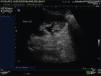

Presentación de los casosCaso 1Masculino de 12 años de edad, con antecedente de infecciones urinarias recurrentes desde los 7 meses de edad. Presenta incontinencia urinaria continua. Es manejado anteriormente con cateterismo limpio intermitente al parecer sin adecuado apego, no mostrando mejoría. Presenta una creatinina sérica de 0.7mg/dL con urea de 49mg/dL, el examen general de orina muestra: leucocituria, bacterias abundantes, nitritos positivos y proteinuria de 300 mg/dL. Presenta un cultivo positivo para Escherichia coli (E. coli) > 100,000 UFC; se indica tratamiento con antibiótico. En la cistografía se evidencia una vejiga de esfuerzo, con reflujo vesicoureteral G-5 derecho y abundante orina residual (fig. 1). El ultrasonido muestra ectasia renal derecha severa y ectasia moderada izquierda (fig. 2). La resonancia magnética de columna se encuentra normal y la valoración por Neurocirugía corrobora que no hay alteración neurológica, la cistoscopia reveló que no hay valvas uretrales. Se realiza ampliación vesical con sigmoides más estoma de Mitrofanoff, se maneja con cateterismo limpio intermitente a través del estoma. En el seguimiento presenta mejoría clínica notable a razón de cese de las infecciones, disminución de ectasia renal (fig. 3), así como desaparición del reflujo vesicoureteral (fig. 4) y continencia completa entre los cateterismos.